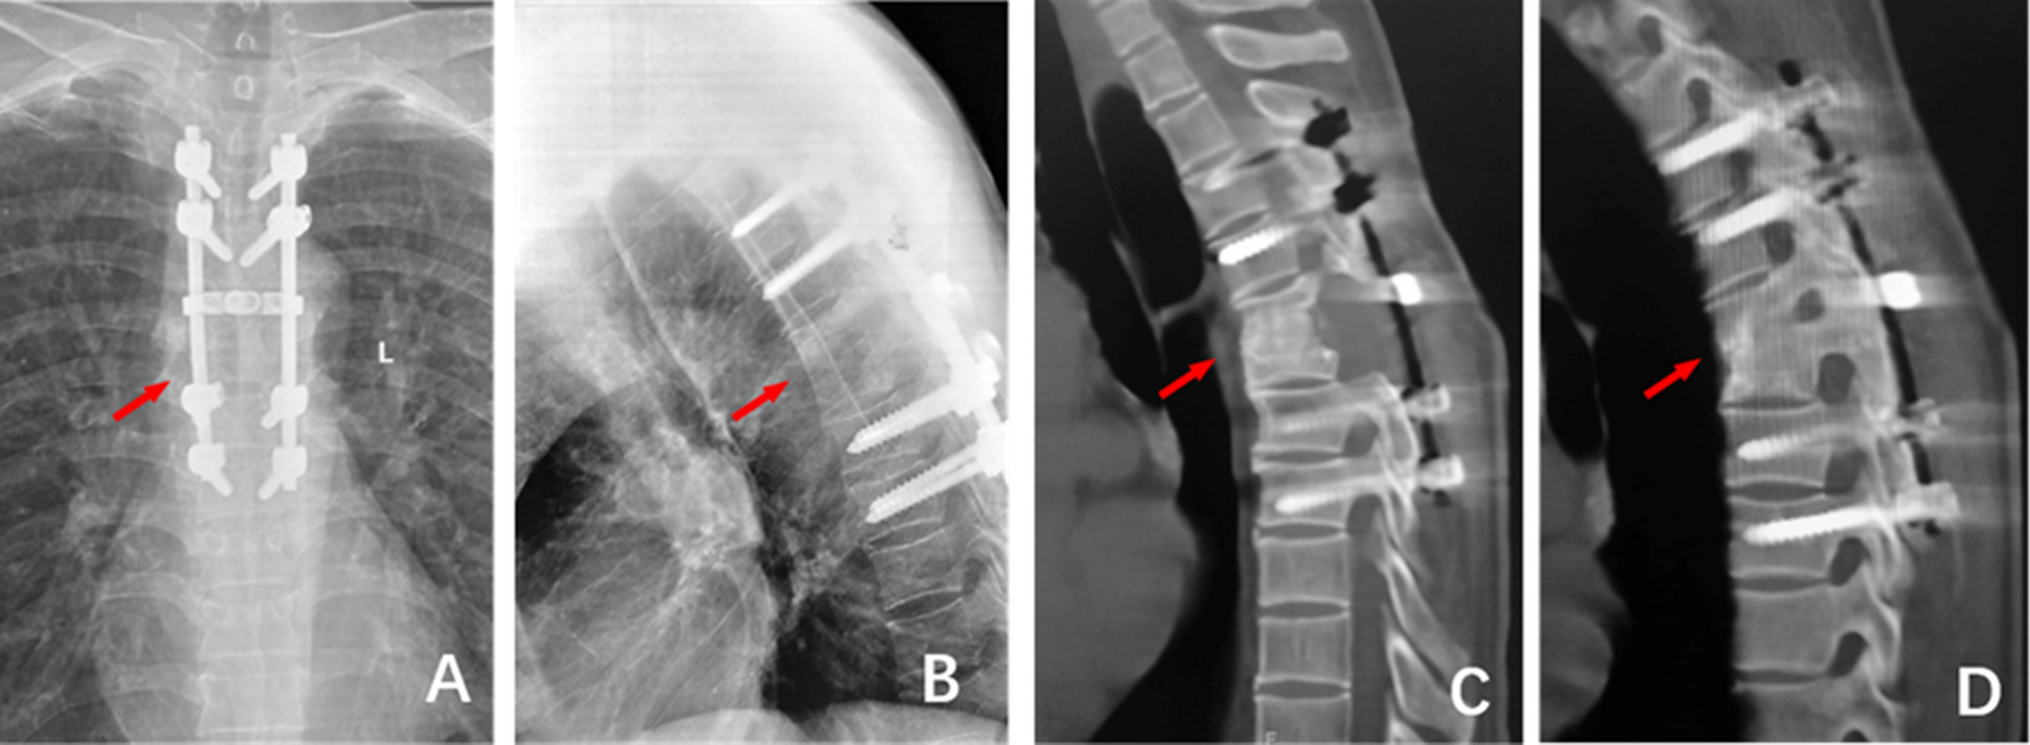

Figure 3

5 years after the operation, (A)and (B) The frontal and lateral X-ray films showed good internal fixation position, bone graft fusion, and Cobb Angle of 20°; (C) and (D): CT examination showed good internal fixation position and bone graft fusion.